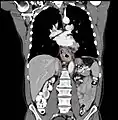

Esophageal cancer (lower part) as a result of Barrettʼs esophagus